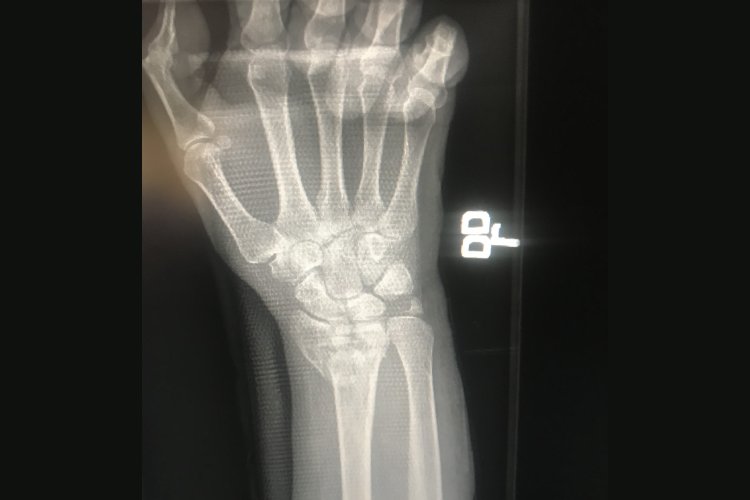

Our practice uses state-of-the-art techniques and technology to treat various types of orthopedic trauma, from work related to personal injuries. We provide the care our patients need for fast, effective, healing and recovery.

At Sean Thompson, MD, Bone & Joint Surgeon, patients receive advanced orthopedic care designed to restore mobility and relieve pain. Led by Sean Thompson, MD, procedures include arthroscopic shoulder surgery, ACL reconstruction, hip and knee replacements, fracture care, and more. With a focus on individualized treatment and state-of-the-art techniques, every patient is guided toward recovery with precision and care. For anyone seeking a skilled orthopedic near me, East Coast Bone and Joint Surgeons provides the trusted expertise needed for lasting relief.